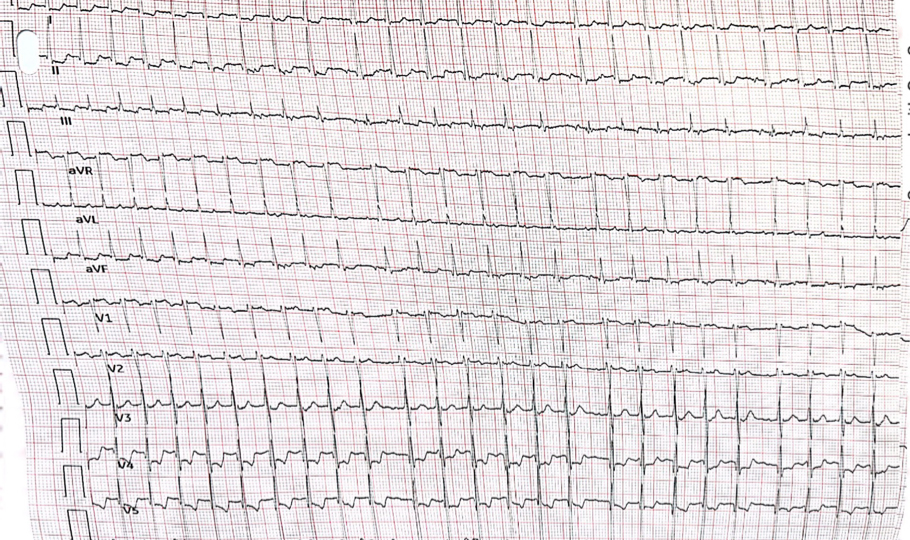

A 16 year old girl with a history of recurrent paroxysmal palpitations and a structurally normal heart has the following 12-lead ECG recorded during an especially severe episode for which she obtained urgent medical assistance.

Haris Haqqani, November 2022